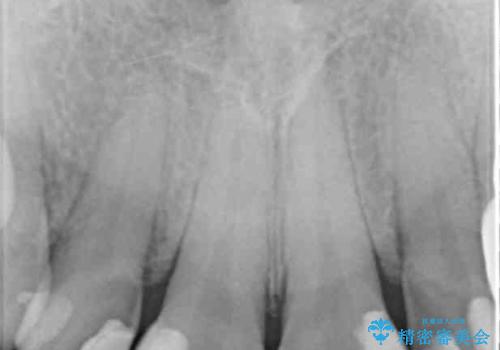

- 矯正治療後に、前歯の樹脂の詰め物のやりかえを提案していましたが、治療は当時行いませんでした。

その後3年間来院がなく、その間に前歯の虫歯の進行があり、治療を行いました。

やはり、樹脂で虫食い状になってしまうと虫歯が進行しやすくなっているためクラウンがおすすめです。

下の前歯との距離(クリアランス)が大きくは取れなかったため、ジルコニアクラウンではなくe-maxクラウンにしました。